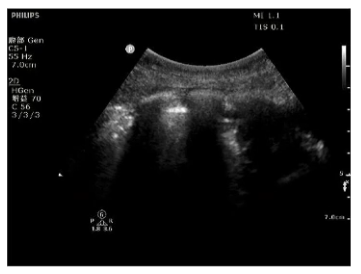

辅助检查:入科第2天行气管镜检查示左肺通畅,右肺大量黄色脓痰(35 ml)(图1)。再行肺部超声检查示右肺点有明显的碎片征,提示右肺实变(图2)。膈肌超声检查示患者右侧膈肌不动,对EDP无反应(图3)。

图2 肺部超声检查

图3 膈肌超声检查

各项检查均提示患者右肺存在问题,且患者右侧膈肌对EDP无反应,是何原因?